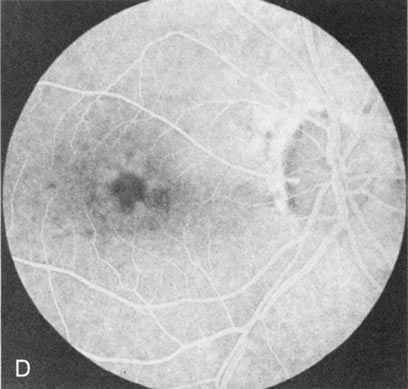

Of more clinical importance is the role of FA in the diagnosis and treatment of cystoid macular edema (CME) (Fig. 1C and D). Stereoscopic FA indicates that the leakage, which may be diffuse or have the typical petaloid stellate appearance of CME, can come from the perifoveal retinal capillaries, from the choroid through the RPE, or from a combination of both sources.4 With the recent suggestion that CME in RP may be successfully treated with acetazolamide,5, 6 FA is thus important to document the diagnosis of CME, establish the origin(s) of leakage, and follow patients during and after therapy.